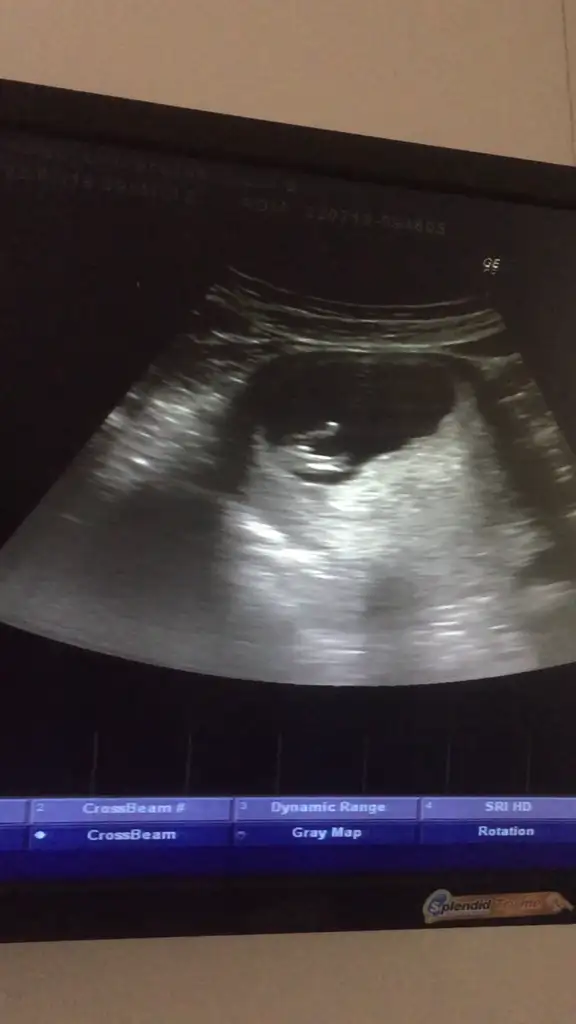

merhaba 12+0 acaba yorumlayabilir misiniz ben cıkintı gormedim

Eklentiler

• 20190722_143243.webp

20190722_143243.webp

19,9 KB · Görüntüleme: 83